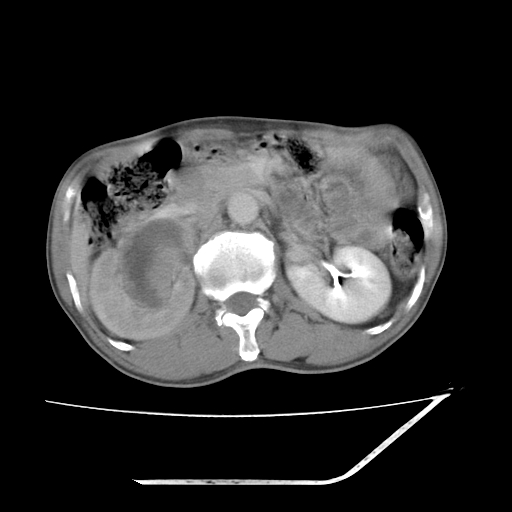

平扫

增强

考虑右肾盂癌,肾动脉受侵,右肾功能减退,右肾盂输尿管积水,管壁增厚,考虑种植转移,应该把下面扫完的

支持右侧肾盂癌伴肾静脉瘤栓形成可能性大,右肾结石.肝右叶后段低密度影,不除外转移.

右肾盂旁ca并肾静脉瘤栓形成/肾功能降低。

右肾结石。

右肾盂癌,肾动脉受侵,右肾盂输尿管积水,管壁增厚,考虑种植转移

支持 右侧肾盂癌伴肾静脉瘤栓形成可能性大,右肾结石;肝右叶后段低密度影,不除外转移。

1.右侧肾盂癌伴肾盂积水。

2.肾脏功能减退,原因有:(1)肾动脉受侵。(2)肾静脉受侵(3)肾积水,等。本例,肾动脉显影较好,但受压明显;肾静脉无明显显示,受压或静脉癌栓,下腔静脉腔内未见明显充盈缺损。

3.右侧上段输尿管扩张,原因:(1)积水所致;(2)种植。